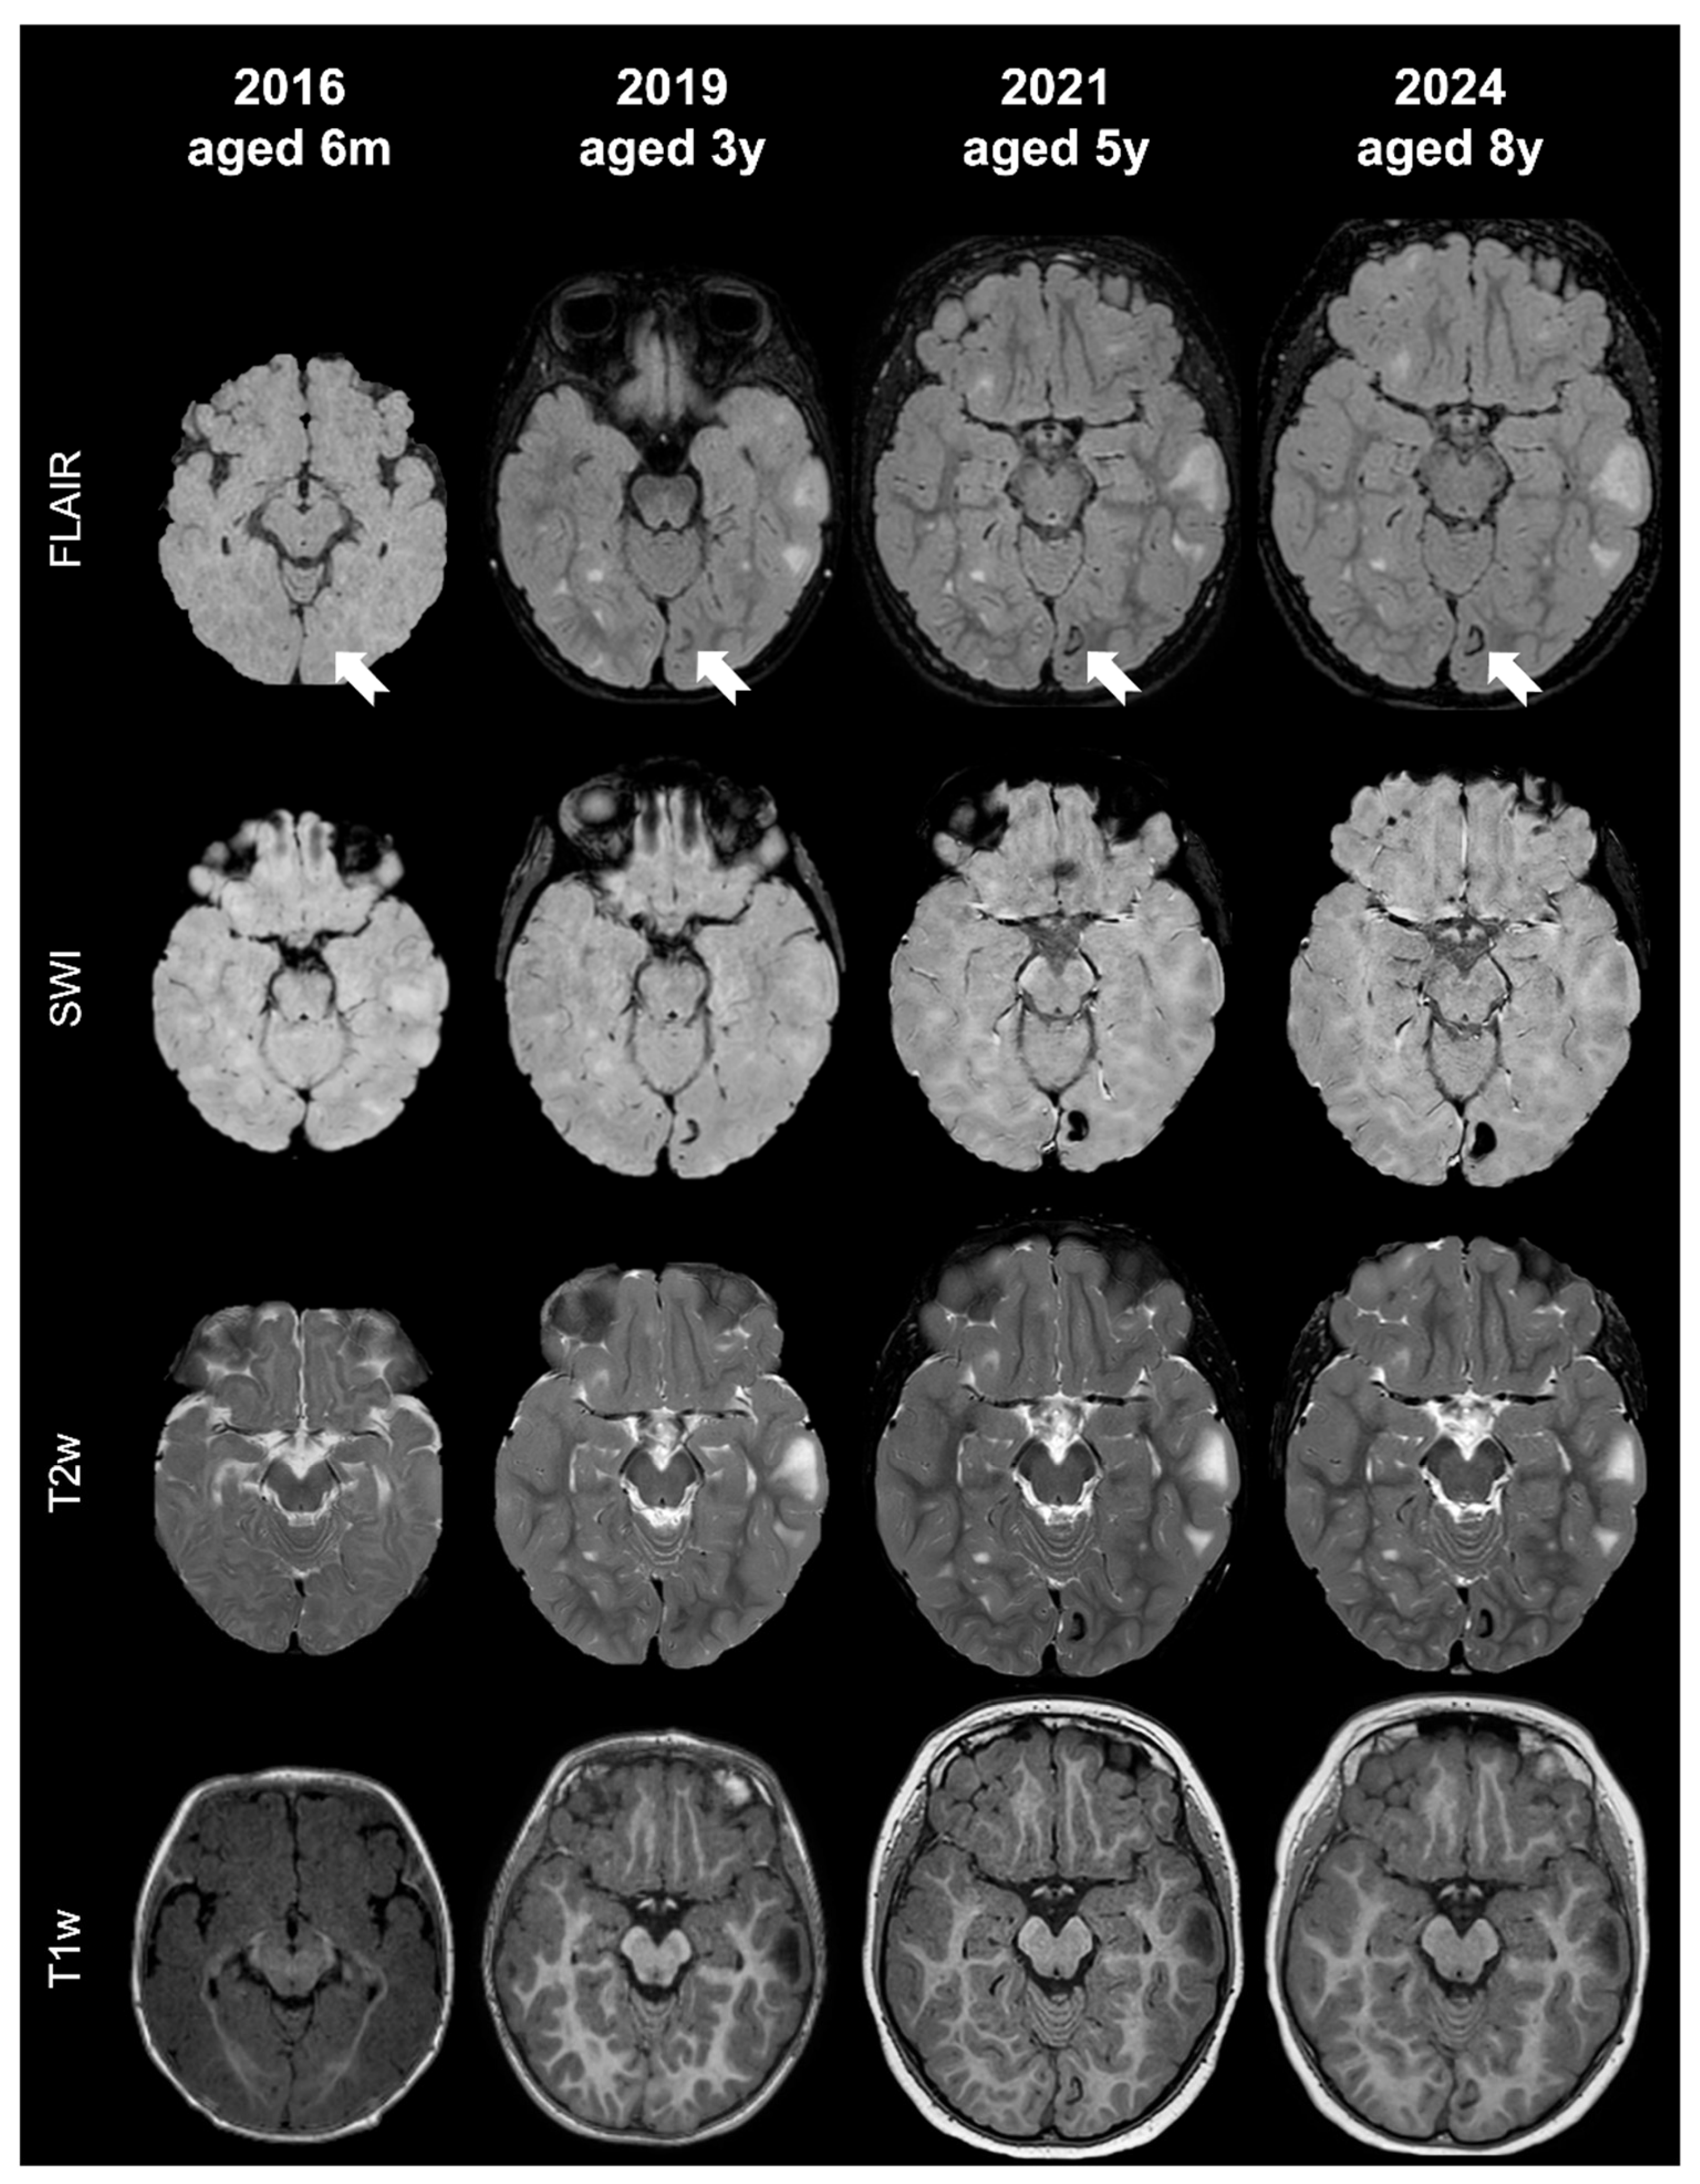

- Tuber C: hypointense on volumetric T1-weighted images and homogeneously hyperintense on T2-weighted images with inner calcifications on SWI, further divided into the following:

- Tuber D: hypointense on volumetric T1-weighted images and homogeneously hyperintense on T2-weighted images with a central cystic area of vacuolization, regardless of the presence of associate calcification(s).

- Tuber C1: with subtle, non-confluent, pinpoint-like calcifications on SWI (micro-calcified)

- Tuber C2: with large, confluent, linear or curvilinear calcifications on SWI (macro-calcified)

- Tuber D: hypointense on volumetric T1-weighted images and homogeneously hyperintense on T2-weighted images, with a central cystic area of vacuolization, regardless of associated calcification(s).

- Russo, C.; Coluccino, S.; De Leva, M.F.; Graziano, S.; Russo, C.; Mazio, F.; De Liso, M.; Cicala, D.; Nastro, A.; Palladino, F.; et al. Cortical Tubers’ Transformation in Pediatric Patients Diagnosed with Tuberous Sclerosis Complex: A Retrospective Longitudinal MRI Analysis. J. Clin. Med. 2025, 14, 7665. [Google Scholar] [CrossRef]